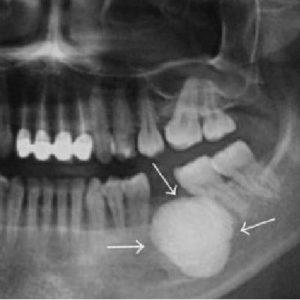

Диагностика данного состояния основывается на результатах рентгенологического исследования.

На рентгеновском снимке отчетливо виден костный нарост, который не срастается с окружающими тканями и имеет четкие контуры.

Важно отметить, что на рентгенограмме экзостоза виден только костный «стержень», в то время как хрящевая ткань не отображается на рентгеновских снимках. В действительности нарост может быть значительно больше, чем на изображении.